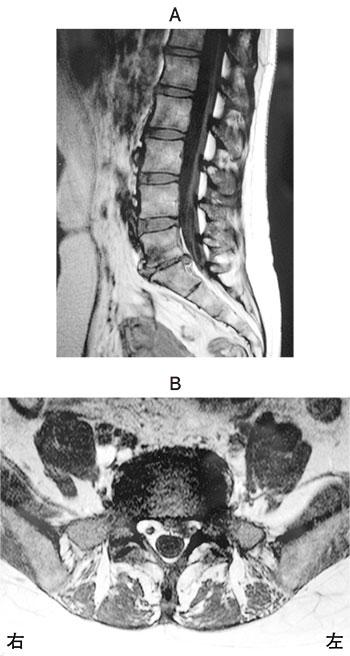

9

理学療法士実地問題 -

第51回 午前

重要度:標準

44歳の女性。1か月前から腰痛および左下肢痛を訴える。腰椎MRIの矢状断像(A)と水平断像(B)とを示す。なお、水平断像は矢状断像で最も所見がある椎体間の高位のものである。この患者にみられる所見はどれか。

1

左下腿内側の感覚障害

2

左足部の感覚障害

3

左大腿四頭筋の筋力低下

4

右下腿外側の感覚障害

5

右長母指伸筋の筋力低下